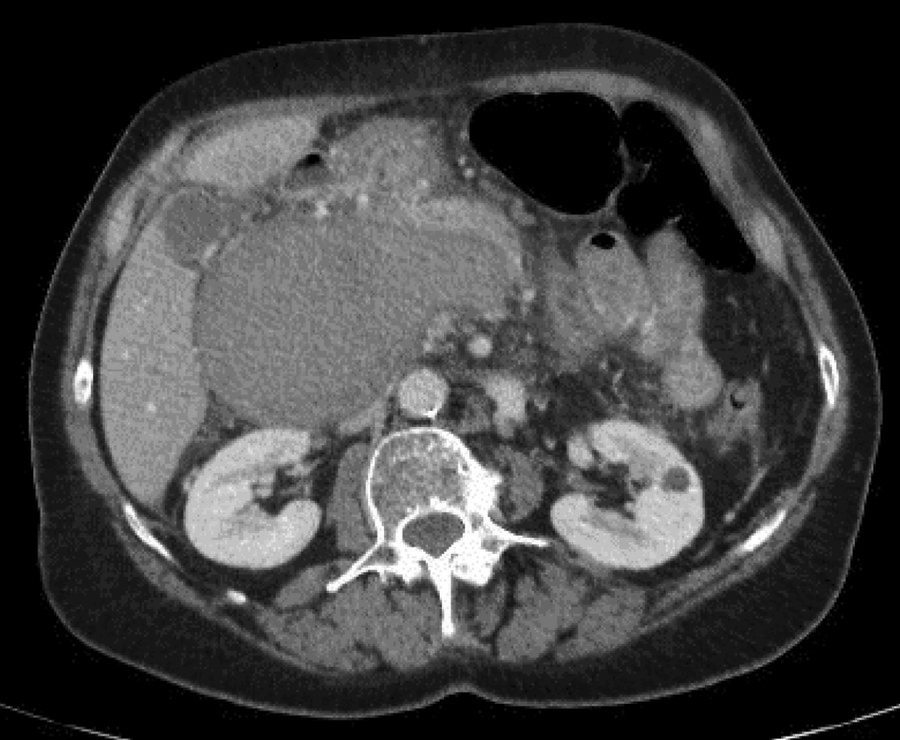

Figure 2

Thrombosed and enlarged portal vein aneurysm.

A 69-year-old female was admitted for moderate epigastric pain lasting for several days. The epigastrium was slightly indurated. The medical history was unrelated. The serum C-reactive protein (CRP) level was 24 mg/L. Abdominal CT obtained 10 years earlier showed a patent portal vein aneurysm (PVA) of 64 mm in diameter with thin margins (Figure 1). Abdominal CT at admission confirmed PVA with a diameter of 79 mm. Native luminal densities of 73 HU corresponded to acute thrombosis (Figure 2). The occlusive thrombus extended into the portal vein branches and into the splenic and superior mesenteric veins. Minimal periportal oedema was present. No thrombophilia was found. Medical treatment included two daily injections of Clexane 60 mg, followed by apixaban 5 mg twice a day for 6 months. Abdominal CT obtained after a follow-up of 14 months showed a reduction of the thrombosed PV diameter to 33 mm, regression of the spleno-mesaraic vein thrombus, recanalisation of the left PV branch and the formation of an extensive periportal cavernoma involving pericholecystic veins (Figure 3). No sign of portal hypertension had developed. The patient remained asymptomatic after 20 months.